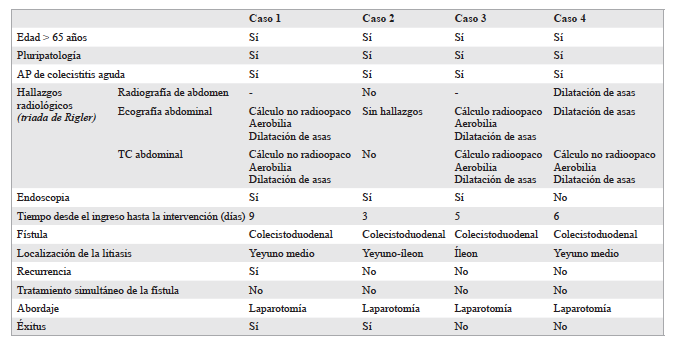

Alberto Vilar Tabanera, Ana Puerta Vicente, Pedro Abadía, Javier Die

|

|

|